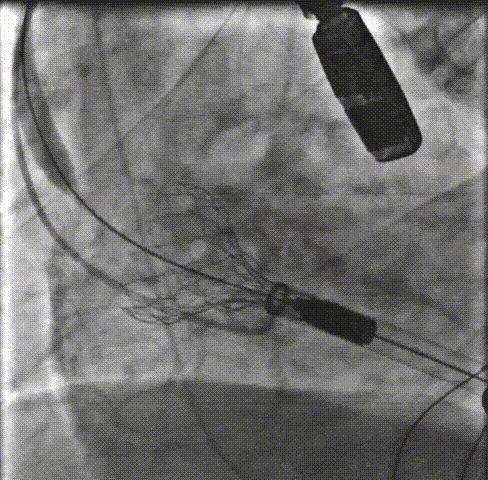

主动脉根部造影:主动脉根部造影可见主动脉瓣运动受限,伴有明显反流,瓣环平面上下可见大量团块状钙化。重度横位心。

预扩张:22mm球囊预扩后,患者出现室颤,电复律后转为窦性。

释放支撑臂:0位匀速释放Xcor-26瓣膜流出端。